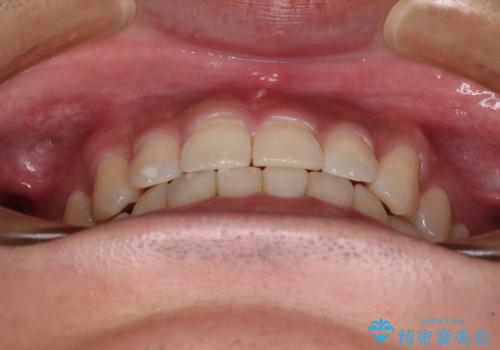

隙間の空いた前歯を治したい 上顎の部分矯正

- 上顎前歯の隙間を気にして来院された患者様です。

下顎前歯に叢生がありましたが、特に気にしていらっしゃいませんでした。

下顎前歯の叢生解消も提案しましたが、上顎の隙間が閉じたことで満足されました。